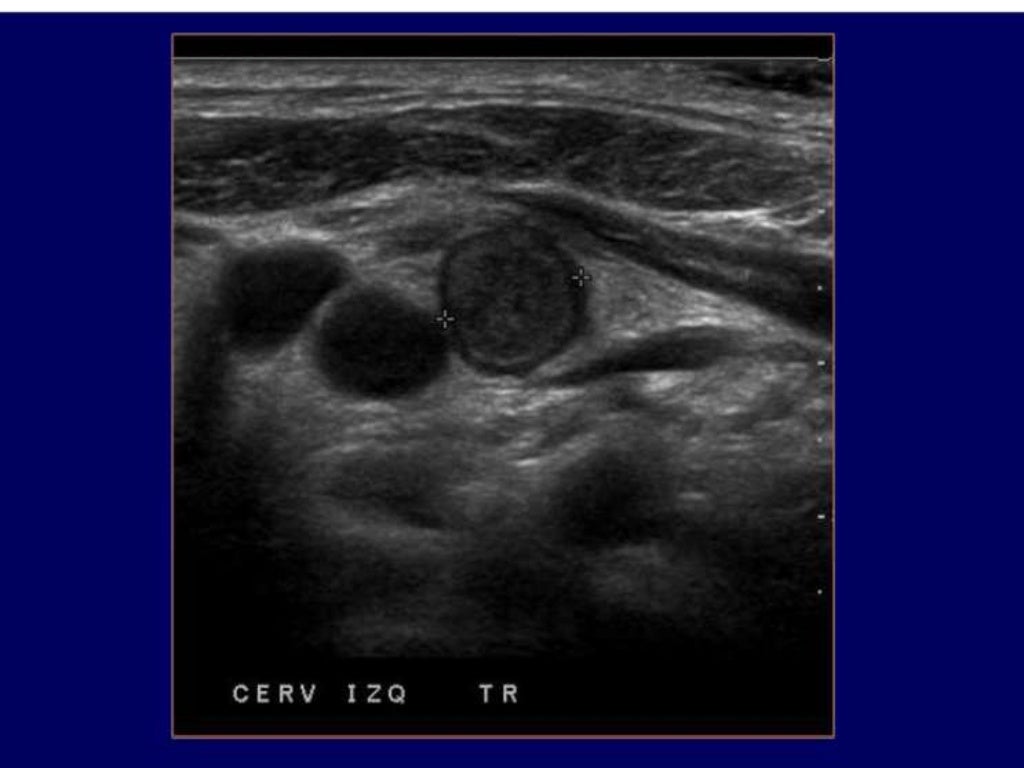

Celulitis o absceso de partes blandas, utilidad de la ecografía para la